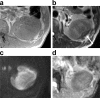

Granulomatosis with polyangiitis (GPA) manifests as necrotizing granulomatous inflammatory masses in the nasal cavity, paranasal sinuses, and lungs. However, a mass in the kidney is extremely rare. We herein report a case of GPA that presented as a solitary mass in the left kidney. The patient was a man in his 60s. A 2.5-cm solitary mass was incidentally discovered in the left kidney at another hospital and was followed-up. Eight months later, the mass had enlarged, and the patient visited our hospital for further examination and treatment. The mass was hypovascular, with unclear margins on contrast-enhanced computed tomography (CT). The signal of the mass was nonuniform and iso- to slightly hypo-intense on T2-weighted and diffusion-weighted magnetic resonance imaging (MRI). Enlarged para-aortic lymph nodes were also detected on the CT and MRI. Based on imaging, malignant tumors were suspected, and nephrectomy was performed. The pathological diagnosis was GPA. We performed a literature review of this rare renal manifestation and present a summary of reported imaging findings. If a hypovascular renal mass with an unclear margin can be found in those with GPA, unnecessary operations may be avoided by actively promoting renal biopsy.